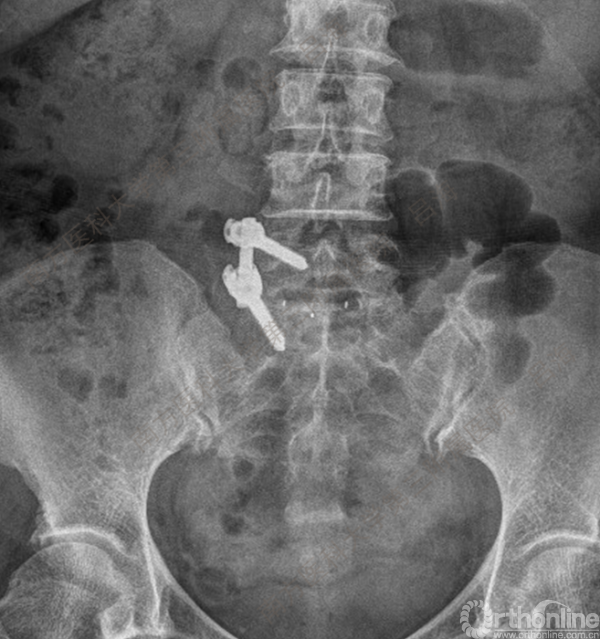

随着社会老龄化进程加快,胸腰椎退行性病变的治疗已经成为脊柱学术界的一个热点话题。MIS-TLIF手术可以治疗多种不同的胸腰椎退行性疾病,南方医科大学第三附属医院吕海教授结合病例为我们一一展示了该术式在治疗不同胸腰椎疾病时的具体手术过程。